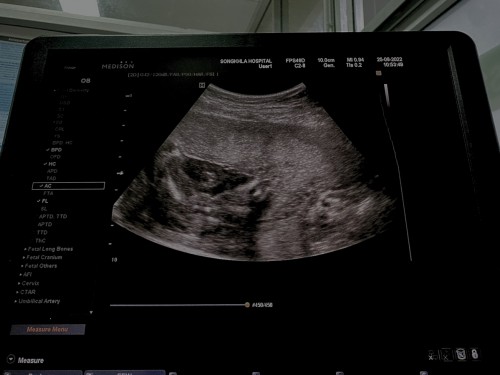

เเม่ๆบ้านไหนได้ลูกสาว มีภาพอัลราซาวตอนดูเพศมั้ยคะ จะเทียบว่าของเค้าใช่หญิงเเน่นอนมั้ยคะ เเต่คุณหมอบอกว่าหญิง❤️

ภาพนี้ตอน15w ค่ะแม่ คุณหมอแจ้งว่าลูกสาว แต่แม่ก็ยังไม่แน่ใจ รอตรวจMFM วันจันทร์ที่จะถึงเพื่อความแน่ใจ

20 W 5 D ค่ะ ตรงที่ชี้เลยค่ะ ลูกสาวค่ะ ถ้าเป็นเด็กผู้ชายจะมีอะไรยื่นออกมา

หมอบอกผู้หญิงคะ20w

หมอบอกผญ.100%ค่ะ